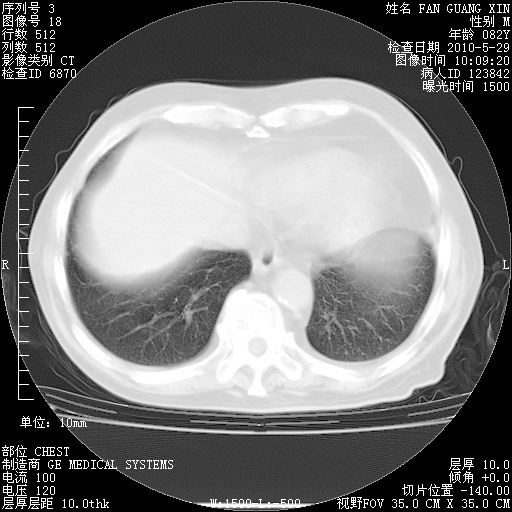

再治疗10天后的肺部CT

阅读此次胸部CT,肺间质渗出性改变较入院时有吸收。目前从体温、白细胞、中性分叶明显增高,肯定存在细菌感染(发生医院感染哦,若无消化道及泌尿系统等感染的依据,肺部感染可能大)。若你院头孢哌酮舒巴坦钠耐药率较高,同意你的方案,若48小时体温仍高,可考虑使用碳青霉稀类抗菌药物,同时可予超声雾化、注意滴数时加大液体量。白蛋白33.30g/L较低哦,需加强营养等支持治疗。